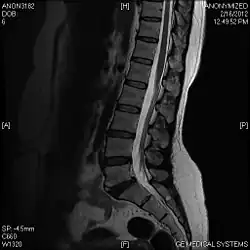

T1 W Sagittal

Limbus Vertebra L5